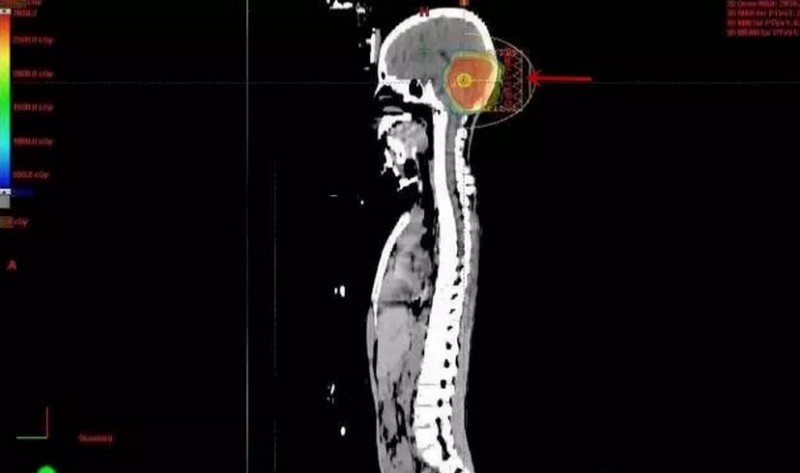

后后颅窝肿瘤区加量质子剂量分布图:其余脑组织未受照射